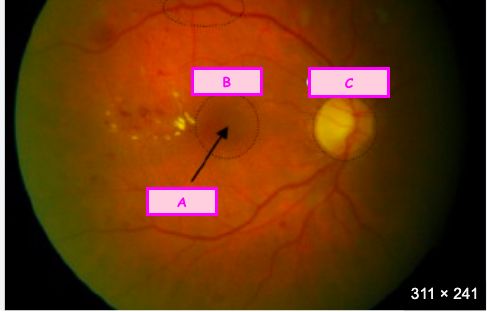

The [] is the innermost layer of the eye

The retina is the innermost layer of the eye

The optic disc is where which two structures join together? [2]

The optic disc is where the optic nerve joins the retina

The [] is the location of maximal photoreceptor density

The macula is the location of maximal photoreceptor density

Label A-C

A: Fovea

B: Macula

C: Optic disc

Optic radiation

The paired optic tracts sweep posteriorly and send most axons to synapse in the [], in the [] nucleus.

The paired optic tracts sweep posteriorly and send most axons to synapse in the thalamus, in the lateral geniculate nucleus of the thalamus.